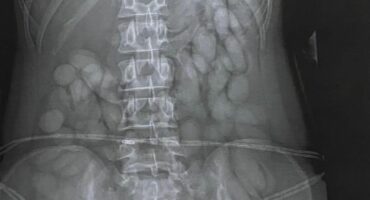

Namibian woman (30) arrested at OR Tambo International Airport

CrimeThe 30-year-old woman was taken to hospital where an X-ray confirmed that she had ingested over 60 'bullets' of suspected…